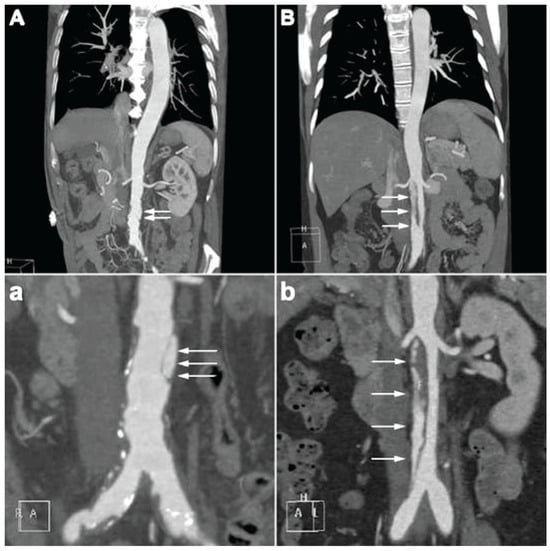

4.2. CTA Imaging Findings